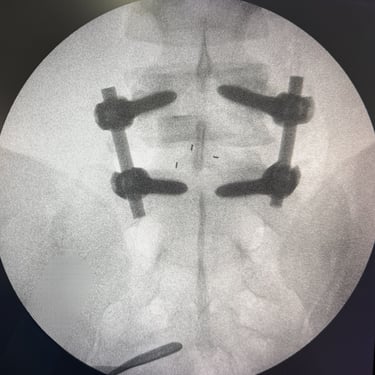

Listesis Lumbar L5–S1 por Fractura Ístmica: Estabilización con FTP y TLIF

La listesis lumbar L5–S1 por fractura ístmica se produce por un defecto en la pars interarticularis que genera inestabilidad vertebral, dolor lumbar crónico y compromiso radicular. Cuando el tratamiento conservador no es efectivo, la artrodesis lumbar con fijación transpedicular (FTP) asociada a la fusión intersomática transforaminal (TLIF) es una alternativa quirúrgica eficaz. Este procedimiento permite descomprimir las raíces nerviosas, restaurar la alineación vertebral y lograr una fijación sólida del segmento afectado. La combinación de estabilización y fusión reduce el dolor, mejora la función y favorece una recuperación segura y progresiva.